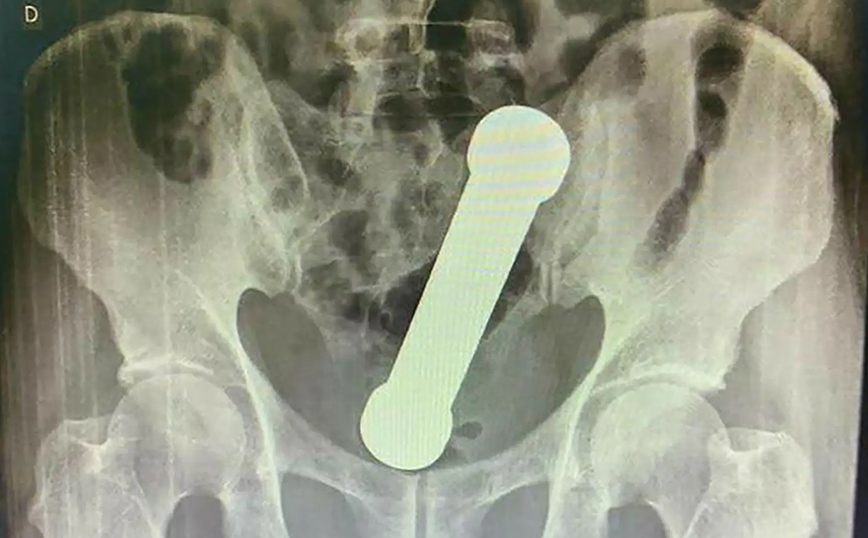

Αφού η αρχική πρωκτική εξέταση δεν αποκάλυψε τίποτα, οι γιατροί αποφάσισαν να σαρώσουν την περιοχή με ακτινογραφία. Ανακάλυψαν έναν αλτήρα μήκους 8 ιντσών που είχε σφηνωθεί στη διασταύρωση του παχέος εντέρου και του ορθού σαν ένα δυσκίνητο σεξουαλικό παιχνίδι.